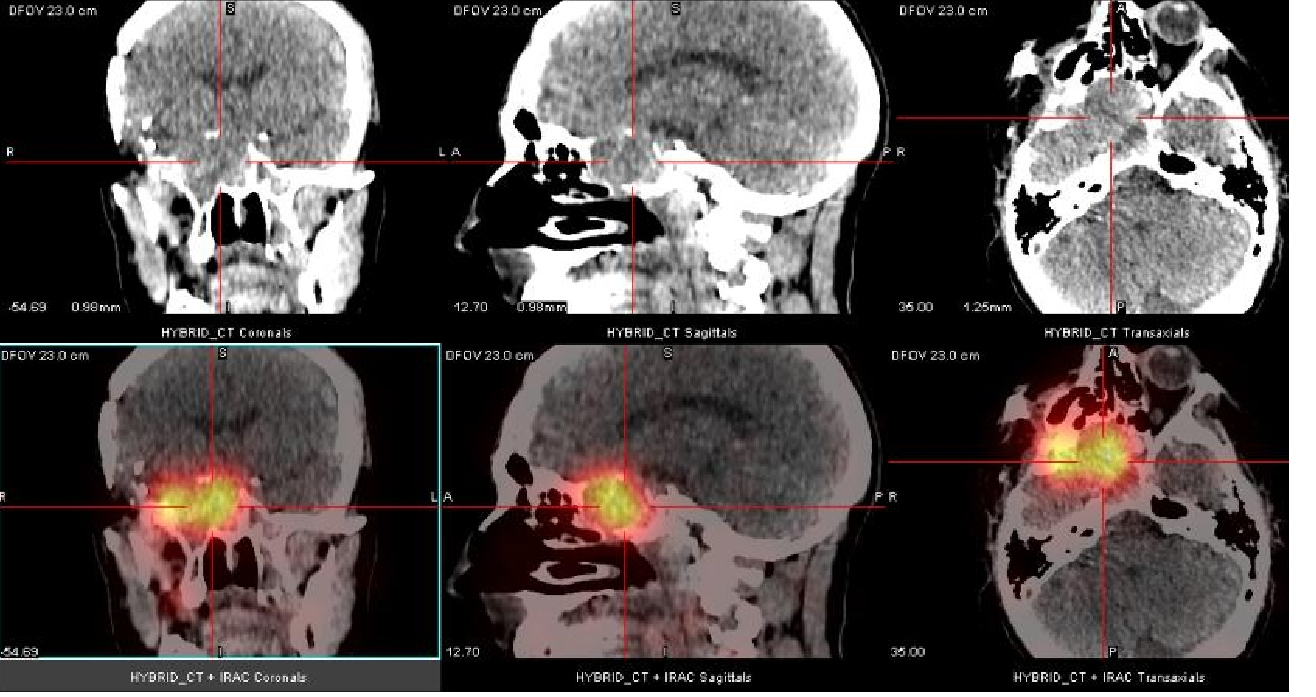

Uma quarta recorrência foi identificada por RM na região retro-orbital direita com progressão ipsilateral anterior para lobo temporal após cinco anos. Investigação pré-operatória constatou uma massa pulmonar na parte inferior do lobo superior esquerdo. Biópsia guiada por CT evidenciou meningioma atípico grau II. Um estudo com 111In-Oct SPECT/CT foi realizado como extensão diagnóstica. Foi evidenciada intensa fixação do 111In-Oct associada à presença de receptores de somatostatina a nível da lesão pulmonar (fig. 1), assim como na lesão temporal direita (fig. 2), confirmando recorrência. Tambén foi detectada fixação linfonodal direita (fig. 3).

Nosso paciente possuía uma lesão intracraniana extensa (47x30x27mm) com metástase pulmonar assintomática. A massa pulmonar foi descoberta incidentalmente durante investigação pré-operatória; uma biópsia pulmonar guiada por CT revelou meningioma atípico. 111In-Oct SPECT/CT caracterizou a massa pulmonar, confirmando, ainda, recorrência local e envolvimento linfonodal.